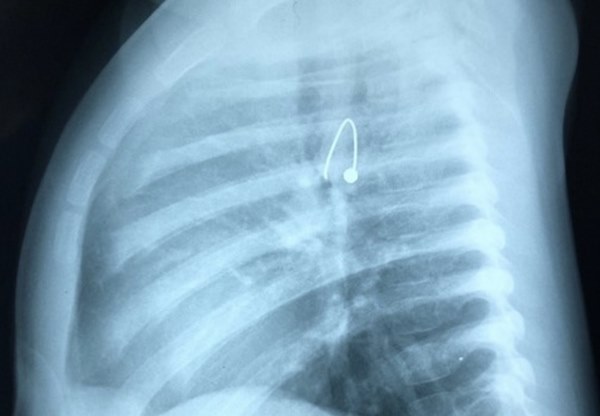

Sau đó bé được chuyển đến BV Nhi Đồng 1 với triệu chứng của đường thở nhưng dị vật ở thực quản.

Tại đây, các bác sĩ tiến hành gây mê soi cấp cứu và gắp được chiếc bông tai cách miệng thực quản khoảng 12cm.

Dị vật có đầu nhọn cắm vào thực quản.

Bông tai có 1 đầu như chiếc kim gâm vào thành thực quản nên rất khó di chuyển.